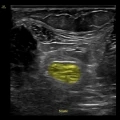

Ecografo POC - Venue GO

GE Venue Go è la versione intermedia della famiglia POC Venue.

Il modulo ecografico carrellato si può separare e usare come portatile. Ha monitor touch da 15,6″, imaging clinico chiaro e strumenti automatici basati su intelligenza artificiale per valutazioni rapide e supporto decisionale in ambienti critici, batterie con autonomia fino a 2 h e superficie facile da pulire per la gestione delle infezioni. È progettato per movimentarsi agilmente nel reparto, con gestione intelligente dei cavi, uso intuitivo e resistenza agli urti.